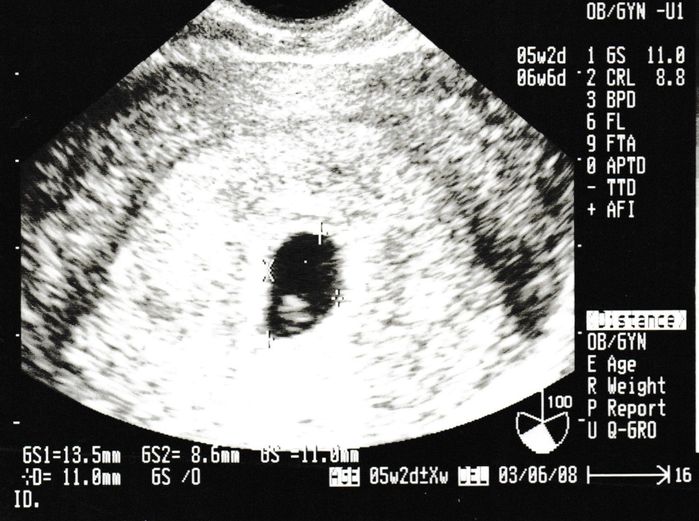

妊娠4週目のエコー写真

生まれて初めての内診。恥ずかしさと、痛みを心配をしている間に終了。胎嚢は確認できたけど、まだ心拍は確認できないので、来週また来てくださいとのこと。また、この時期は初期流産の可能性も高いという話をされて、一気に心が沈みました。確かに、普通なら妊娠に気づかないような超初期。でも、確実に命の始まりがあることがわかり、「流産はしたくない!」と思い続けて過ごしました。